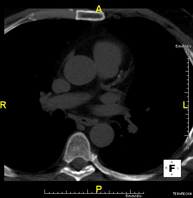

Multidetector Computed Tomography

Thorax

Diagnostic test that measures the amount of calcium that may have accumulated in the atherosclerotic plaques of the coronary arteries using state-of-the-art MDCT equipment. It is a non-invasive test that does not require iodinated contrast. No prior preparation is necessary. Calcified plaques are detected using a specialised workstation that allows the exact amount of calcium to be quantified and given a score, which is known in medical practice as the calcium score.